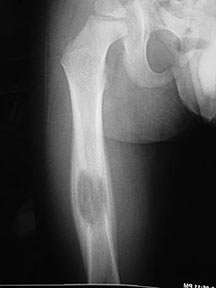

- May arise from any bone and any site within a bone (epiphyseal, metaphyseal, diaphyseal)

- Radiographically variable appearance: may appear benign (geographic) or malignant (permeative or moth eaten)

- Femur